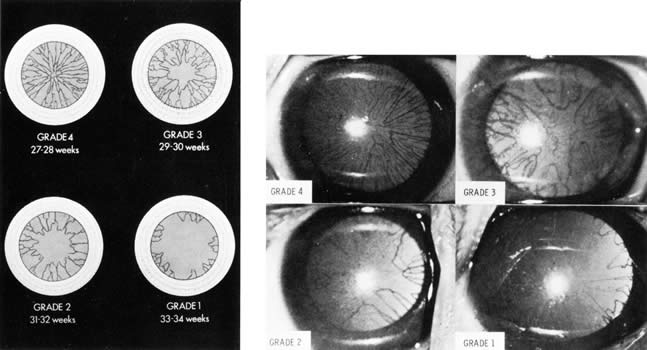

of the lens. J Pediatr 91:455, 1977 200. Hittner HM, German WA, Rudolph AJ: Examination of the anterior vascular capsule of the lens, Part II. Assessment

of gestational age in infants small for gestational age. J Pediatr Ophthalmol Strabismus 18:52, 1981 201. Mimouni F, Nissenkorn I, Wilunski E, et al: Assessment of gestational age by examination of the anterior vascular capsule

of the lens: Value in multiple pregnancy (quintuplets). J Pediatr Ophthalmol Strabismus 20:27, 1983 202. Hittner HM, Speer ME, Rudolph AJ: Examination of the anterior vascular capsule of the lens. Part III. Abnormalities

in infants with congenital infection. J Pediatr Ophthalmol Strabismus 18:55, 1981 203. Hiles DA, Wallar PH, MacFarlane F: Current concepts in the management of strabismus in children with cerebral